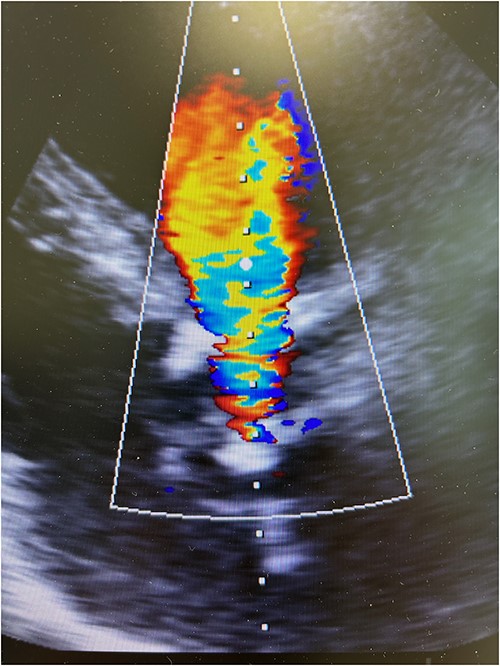

Resternotomy was undertaken and the aortic root was dissected free of considerable adhesions. The aortic arch and the remnant of the right atrial appendix were cannulated to initiate cardiopulmonary bypass and retrograde cardioplegia was administered after cross-clamping of the aortic prosthesis, which was thereafter transected immediately distally to the previous proximal aortic suture line. Care was applied while the destroyed aortic valve prosthesis and the coronary ostia were dissected free from the left outflow track encompassing the calcified annular structure, pledgets, and suture material. Though the aortic root remained intact after surgical revision, the remnant aortic valve annulus was torn and an intramyocardial defect was evident beneath the left and right coronary ostia. A size 23 mm rapid-deployment Edwards Intuity bioprosthesis was implanted with the aid of three guiding sutures that also ensured the integrity of the coronary ostia. The skirt of the prosthesis was raised up and the aortic valve prosthesis was well fit despite the revision lesions and intramyocardial calcium of the left outflow track beneath the old aortic valve annulus. After surgical closure of the supracoronary aortic prosthesis and weaning from cardiopulmonary bypass, echocardiography revealed a well-seated aortic valve prosthesis with a trace of paravalvular leak (Fig. 3). The patient experienced minimal weakness of the left arm during an otherwise uneventful recovery without cerebral lesions observed by computed tomography. Clopidrogel was readministered and the patient was dehospitalized after 10 days of surgery.

Postoperative transesophageal echocardiography showing nonsignificant regurgitation of a well-seated rapid-deployment Edwards Intuity bioprosthesis.